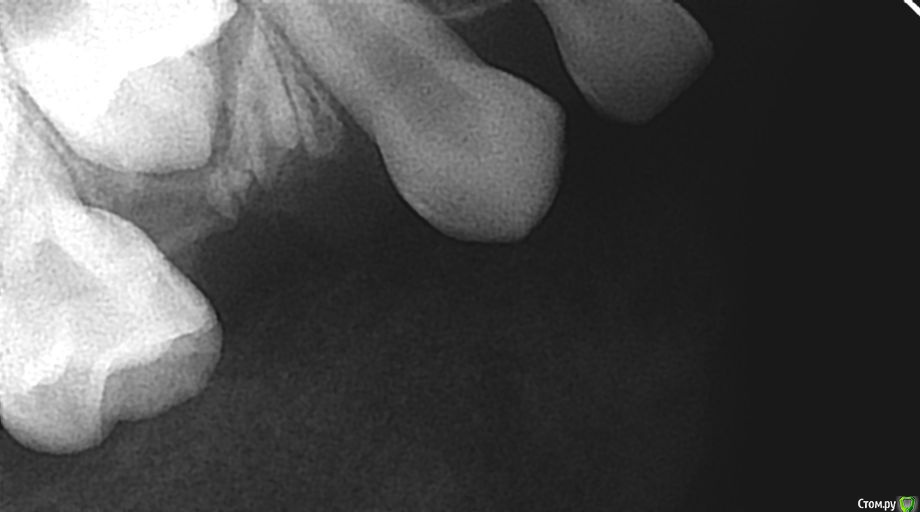

alin8888 Опубликовано 6 января, 2018 Автор Поделиться Опубликовано 6 января, 2018 Что объяснить?Мы ситуацию только с Ваших слов видим. Давайте снимки до и после, тогда уже будем понимать о чём идёт речь.Для того, чтобы не было смещения зубов на место удаленного, обратитесь к ортодонту, профилактические конструкции легко переносятся детьми.снимки есть, один сделан до удаления, другой после.Какой до, какой после не понимаю. Но мне еще раз сегодня сказали, что если уже пошло восполнение,которое проявилось в виде опухшей щеки ,восполненных десен- удаление . Ссылка на комментарий

alin8888 Опубликовано 6 января, 2018 Автор Поделиться Опубликовано 6 января, 2018 (изменено) второй снимок Изменено 6 января, 2018 пользователем alin8888 Ссылка на комментарий

alin8888 Опубликовано 7 января, 2018 Автор Поделиться Опубликовано 7 января, 2018 хотелось бы получить ответ из данных снимков.спасибо Ссылка на комментарий

сирена Опубликовано 7 января, 2018 Поделиться Опубликовано 7 января, 2018 Вам же дали ответ:мезиальный корень остался,со временем "выползет" на поверхность,можно будет его атравматично удалить.Если другие врачи не пишут,значит добавить нечего.У нас ответы на вопросы пациентов - дело добровольное. 1 Ссылка на комментарий

alin8888 Опубликовано 7 января, 2018 Автор Поделиться Опубликовано 7 января, 2018 насчет корня понятно. По снимкам действительно, только удаление? Отправила снимки,чтобы не было только с моих слов... Ссылка на комментарий

Brigita Опубликовано 7 января, 2018 Поделиться Опубликовано 7 января, 2018 Да, только удаление. Врач сделал все верно. 2 Ссылка на комментарий